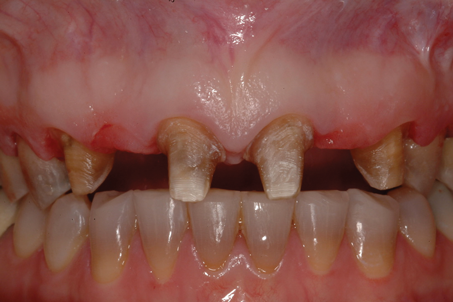

(7.) Pretreatment retracted close-up view of two defective 3-unit fixed partial dentures spanning teeth Nos. 6 through 8 and teeth Nos. 9 through 11.

Figure 7

A patient presented with two defective 3-unit fixed partial dentures spanning teeth Nos. 6 through 8 and teeth Nos. 9 through 11 (Figure 7). The defective fixed partial dentures were removed (Figure 8), an impression was made, and traditional provisional fixed partial dentures without ovate pontics were placed. After the impression was sent to the laboratory, the lab technician prepared ovate pontic sites on the stone cast (Figure 9) and fabricated the new definitive bridges. On the day of insertion, the provisional fixed partial dentures were removed (Figure 10), ovate pontic sites were prepared using a teardrop-shaped diamond bur (Figure 11), and the sites were sounded to confirm that there was at least 2 mm from the base of the pontic site to the alveolar bone (Figure 12). The fixed partial dentures were cemented, and the postoperative healing was uneventful (Figure 13).